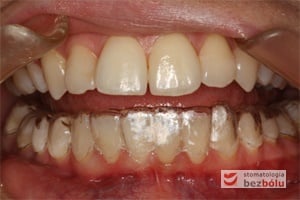

- Wygodne – brak metalowych elementów drażniących błonę śluzową, które są niewygodne i utrudniają higienę. Niedostateczna higiena z kolei prowadzi do demineralizacji i plam wokół zamków jako odwapnienia, a w skrajnych przypadkach mogą być przyczyną próchnicy.

Szyna powinna być noszona minimum 20 godzin na dobę, zdejmować ją należy do spożywania posiłków i zabiegów higienicznych. W sytuacji dużej wady i konieczności znacznych przesunięć zębów jeden pozycjoner może być niewystarczający i należy zastosować serię nakładek prostujących zęby. Po zastosowaniu trzech kolejnych szyn pacjent powinien zjawić się na wizytę kontrolną. Konieczna jest dyscyplina pacjenta, zgłaszanie się na regularne wizyty kontrolne i stosowanie się do zaleceń odnośnie retencji, mającej na celu utrwalenie efektów leczenia.